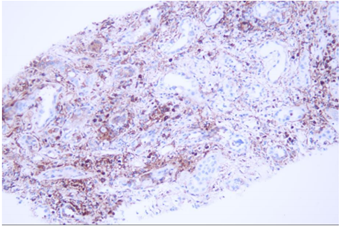

病理诊断:

符合急性间质性肾炎,肾间质可见大量浆细胞,建议临床注意排查IgG4相关肾损伤。

免疫组化:CD38:肾间质多灶状细胞阳性;IgG:肾间质灶状细胞阳性,IgG4:肾间质小灶状细胞阳性,局灶>10个/HP,IgG4/IgG浆细胞比率>40%